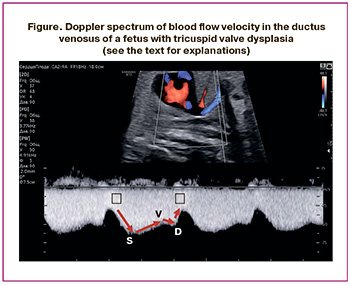

Studies conducted both domestically and internationally have shown a significant increase in the risk of placental dysfunction and premature birth among pregnant women diagnosed with fetal cardiac pathology compared to population data and control groups. Furthermore, there is a linear positive correlation between prematurity, asphyxia, and low birth weight and the likelihood of unfavorable outcomes for the child [6–11]. However, in our country, clinical recommendations for the dynamic monitoring of fetuses with various hemodynamic types of CHD have yet to be developed, similar to those already implemented in global practice, where assessing blood flow in the ductus venosus is an integral part of functional prenatal echocardiography [12, 13]. Analyzing the blood flow velocity curve in the ductus venosus allows us to summarize the data on the hemodynamic state of the right heart. The values of the waves in the Doppler spectrum reflect rapid changes in the pressure gradient between the umbilical vein and right atrium during ventricular systole and diastole, as well as atrial systole, throughout the cardiac cycle [14, 15]. It has been established that the S-wave and v-wave occur during ventricular systole, while the D-wave and a-wave appear during ventricular diastole (Figure) [16]. The S-wave reflects an increase in flow through the ductus venosus due to a drop in pressure in the right atrium during the lowering of the atrioventricular (AV) valve rings and ventricular contraction. In late ventricular systole, as the AV valve rings rise, the pressure in the atria increases, leading to a decrease in inflow through the venous duct, corresponding to the v-wave on the blood flow velocity curve. In early ventricular diastole, the AV valves open, the pressure in the atria drops, and the flow velocity in the ductus venous increases, forming the D-wave. In late ventricular diastole, atrial contraction raises the pressure in the atria, reduces inflow through the venous duct, and corresponds to the a-wave on the blood flow velocity curve. The qualitative assessment of the a-wave, particularly regarding the presence of direct (positive), zero, or reverse (negative/reverse) flow during atrial contraction, is most often analyzed in routine obstetric ultrasound examinations.